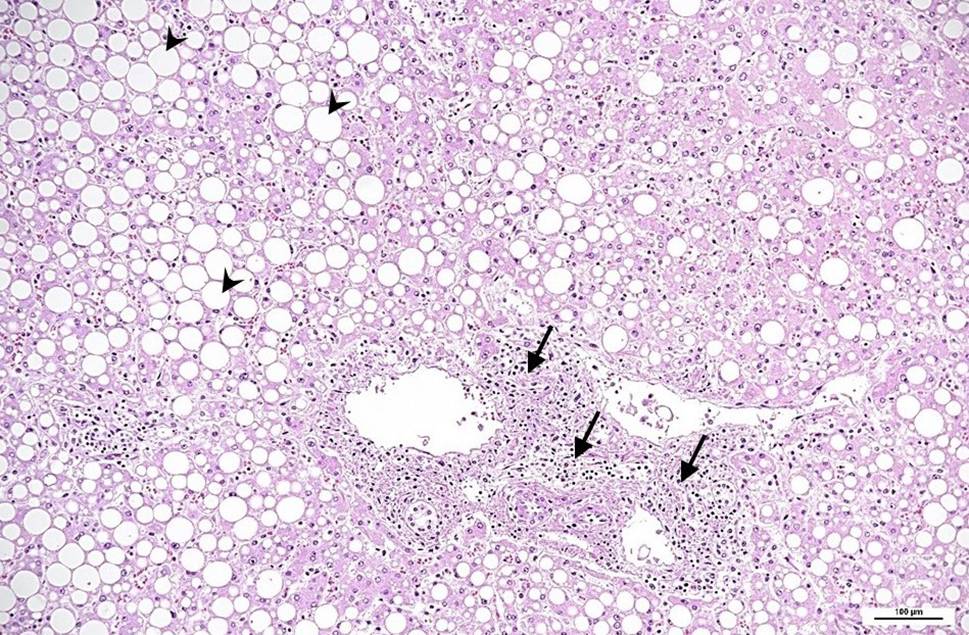

Fig. 1

Liver histology: portal field with mild lymphocytic infiltration (arrows); massive, predominantly macrovesicular steatosis (arrowheads). Hematoxylin and eosin, original magnification 100 ×

The peritoneal cavity contained 150 mL of turbid fluid. The liver was enlarged with a coarse border and multiple irregularly distributed bright yellow areas in the liver capsule (suspicious of ischemic areas). It weighed 2.5 kg. Histology showed massive steatosis (grade 3) with moderate inflammatory infiltration of the portal fields, and portal and focal septal fibrosis (stage 1), but no evidence of viral hepatitis (Fig. 1). The serosa of the bowel was covered and clotted with fibrin; histology showed massive infiltration with neutrophils and multiple bacteria, mainly of coccoid structure, which is typically found in fibrinous-putrid peritonitis (Fig. 2). The kidneys appeared normal on gross examination and displayed focal interstitial lymphocytic infiltration and mild arteriosclerosis on histology. The spleen, pancreas and stomach were macroscopically and histologically unremarkable.